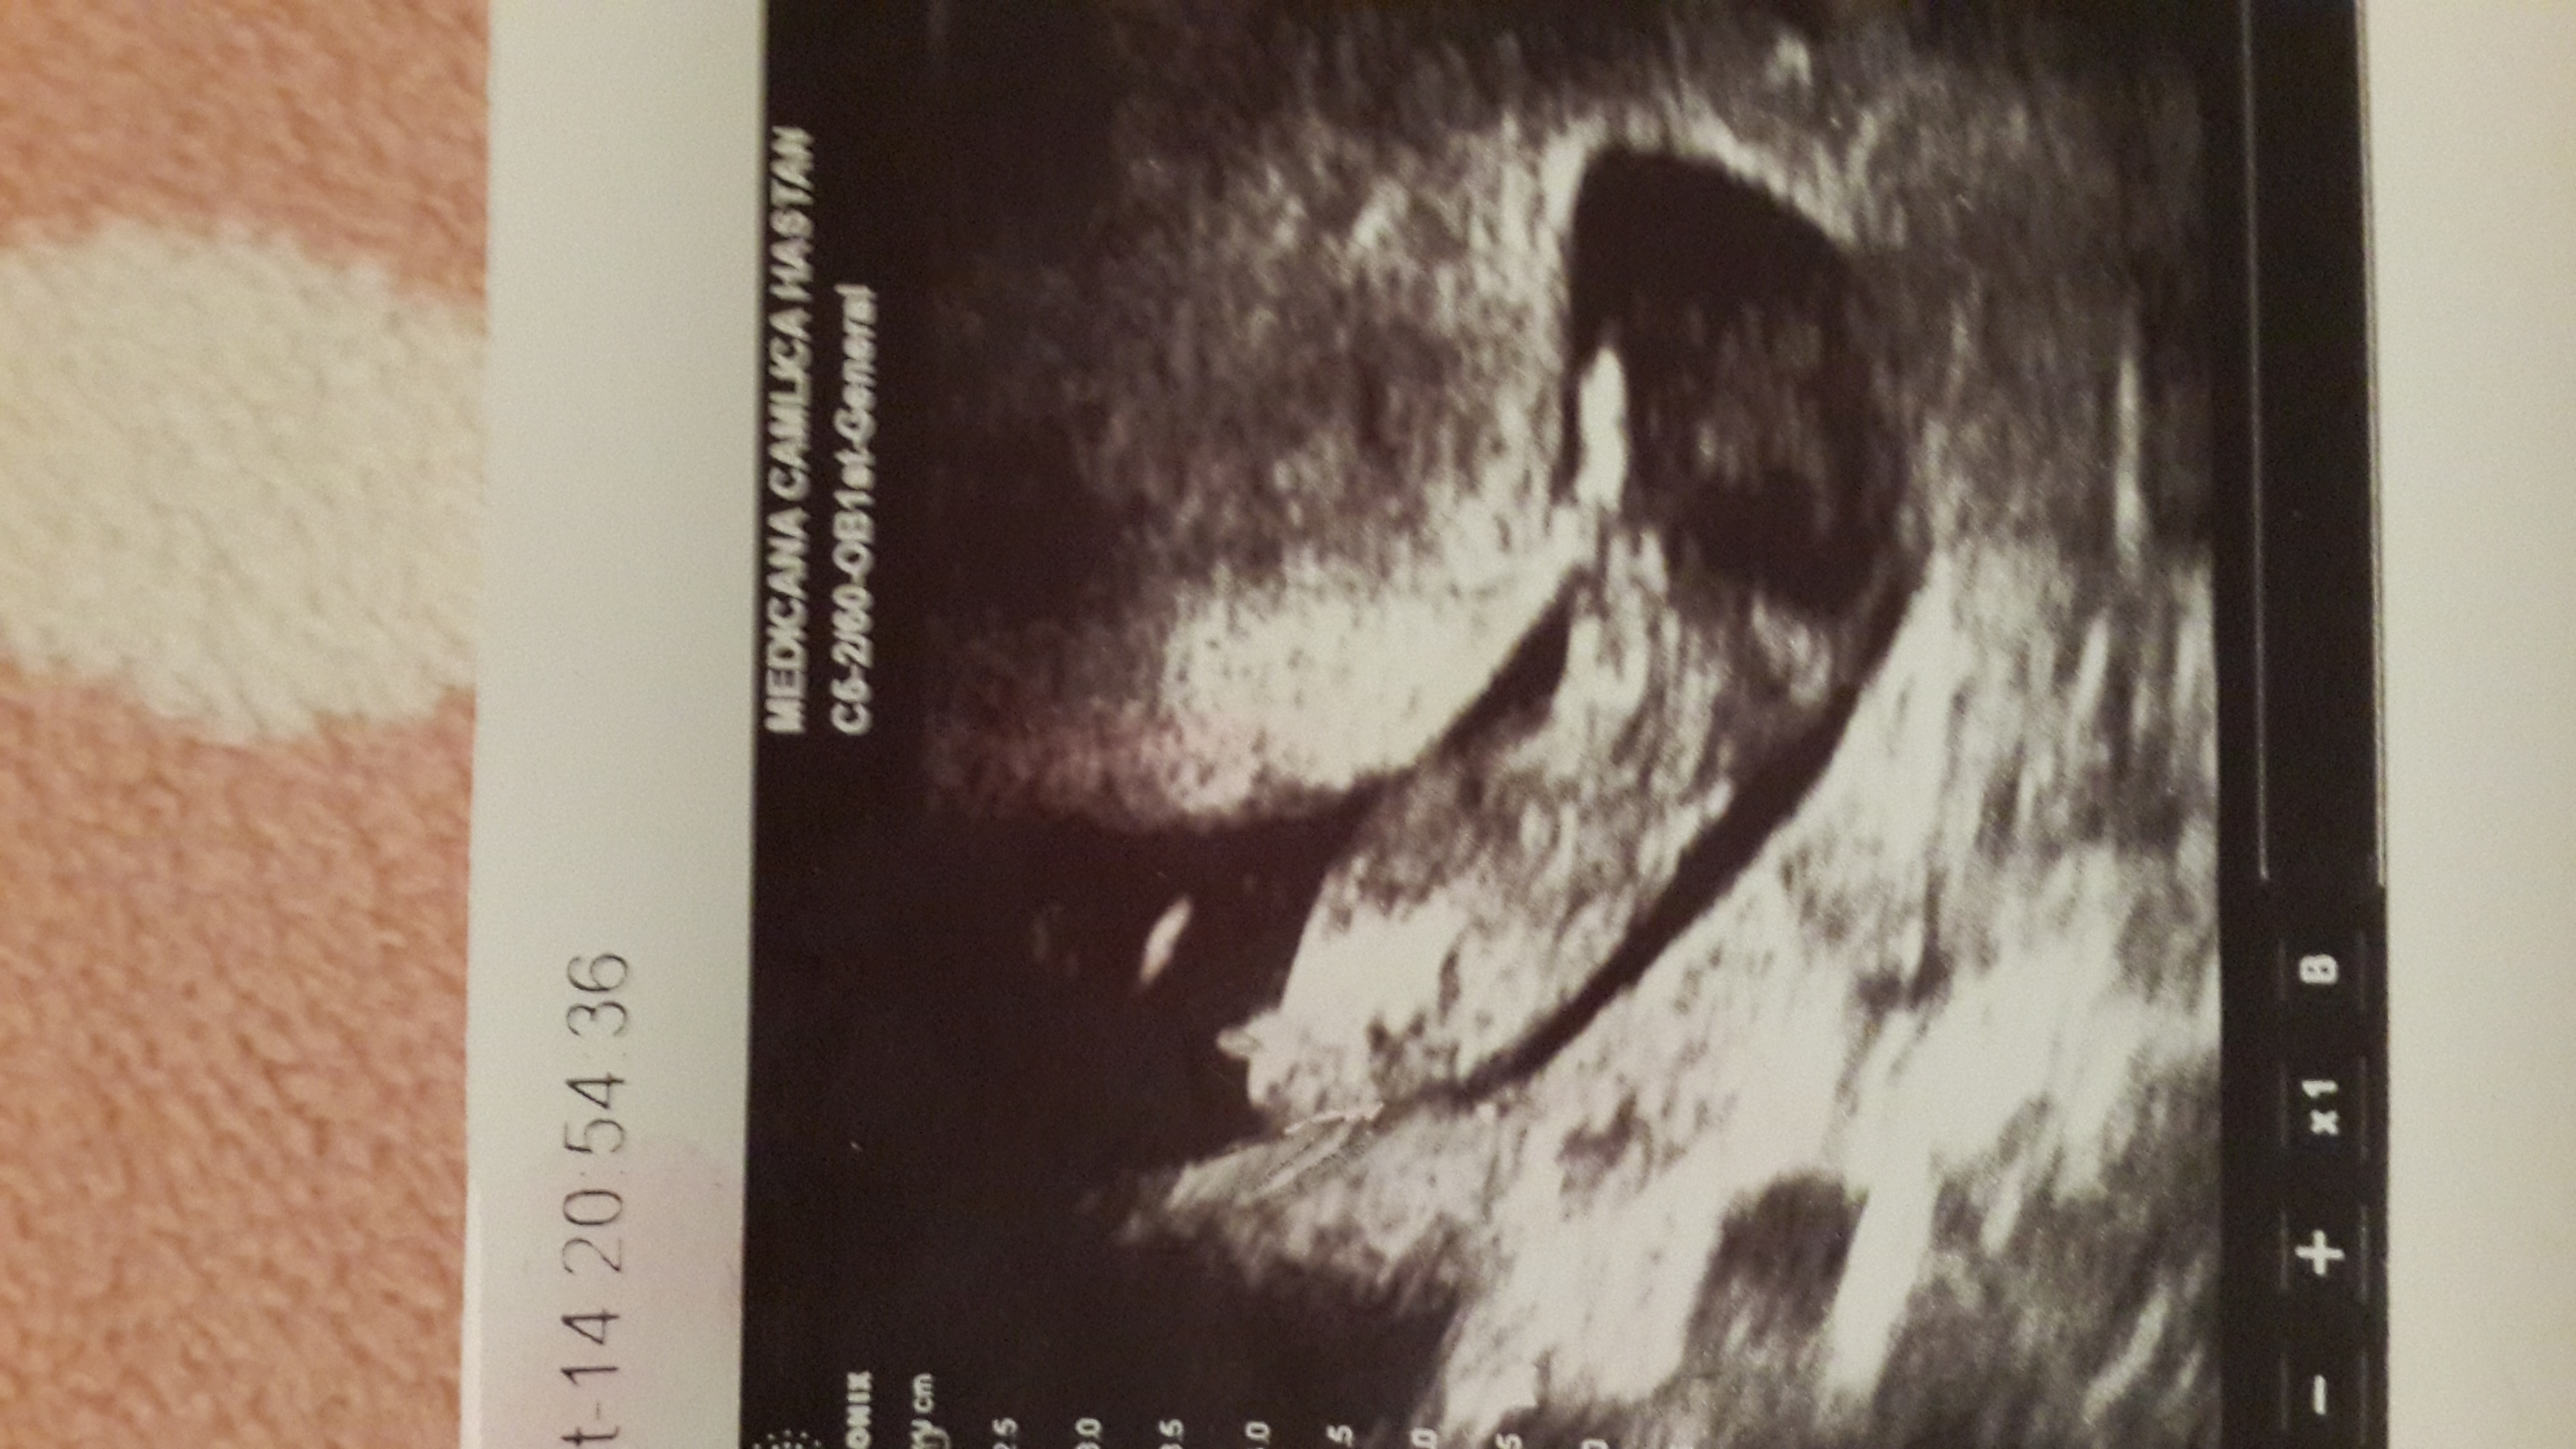

Hi ladies:) would be really appreciate if any guess about my pict. 12w+2us

Not a great profile pic but will give a boy guess :)

Maybe boy

leaning blue